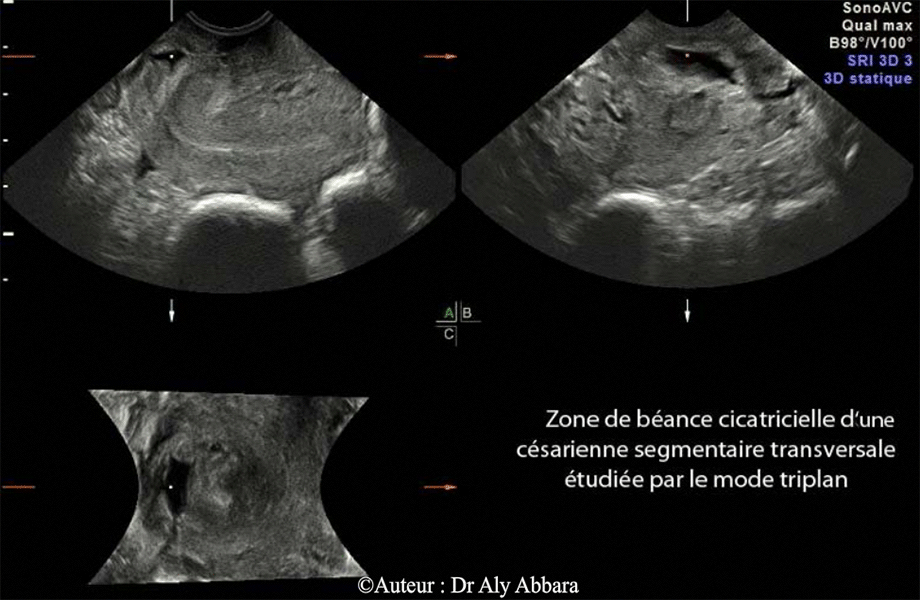

Utérus cicatriciel - Isthmocèle - Echographie mode Triplan

Cicatrice d'une césarienne segmentaire transversale identifiable par l'échographie 3D, mode "Triplan" ; ce mode permet d'explorer cette cicatrice dans un plan sagittal, puis transversal et frontal.

Il s'agit d'une cicatrice béante et prenant, sur la coupe sagittale, l'aspect d'une zone anéchogène, profonde et triangulaire, située dans la paroi antérieure de l'isthme utérin et communiquant avec la cavité utérine. Sur les coupes transversale et frontale, on constate qu'il s'agit d'une fissure profonde (ou solution de continuité) étendue sur toute la largeur de la paroi antérieure de l'isthme utérin, mais en profondeur, il persiste une fine couche non fissurée de cette paroi.